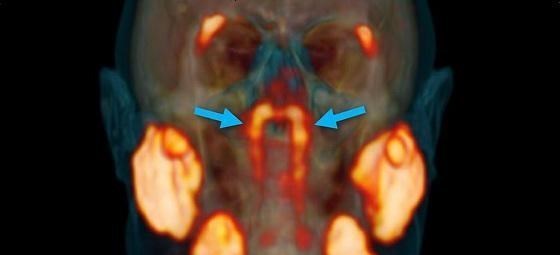

生物学家 , 在对癌细胞进行研究的过程中 , 在无意的情况下竟然发现了人的鼻子到咽喉的深处 , 竟然有一对前所未有的奇观 , 非常的小大 , 仅仅只有3.9公分 , 而这个器官其实就是唾液腺 。

除此之外还有1000个以上的小唾液腺分布在口腔以及后喉咙的黏膜组织当中 , 可是鼻腔的后方竟然还有一对大的主要的唾液腺 , 这一点让所有的科研人员为之兴奋 。

最后通过扫描追踪放射性失踪剂 , 就能够准确的得知癌细胞所处的位置 , 而这种利用失踪剂成像诊断法又被称之为“PSMA PET-CT” 。

然而PSMA这种蛋白质不仅存在于前列腺癌细胞当中 , 在人体的唾液腺组织中也发现了些踪影 , 所以说在成像扫描的过程中就特意标出了人体当中所有唾液腺的位置 。

正是因为在这种情况下才意外地发现了新的唾液腺 , 并且直接命名为“Tubarial Glands (管状腺)” 。

后来根据调查研究发现这个新的器官并不是某些人特有的 , 因为在对100名志愿者进行了PSMA PET-CT之后都发现了这个器官的存在 , 而这也就表明了这个器官完全就是人体的标配 。